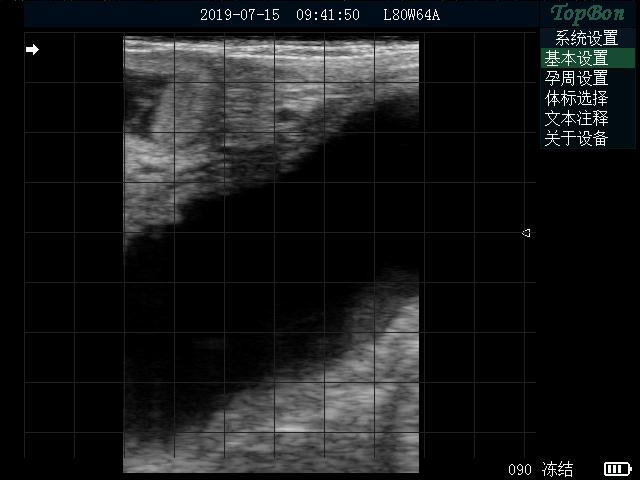

首先要給牛固定,最好有限位欄,防止被牛踩到。接下來給牛掏糞,因為牛的糞便會影響B超使用效果。第三步,手持B超探頭從牛的肛門伸入體內,伸入距離大概到手的肘部位置,用手按壓探頭,使B超聲窗和直腸緊密接觸,然后聲窗左右來回擺動,觀察到牛的子宮或者胎仔停止擺動,仔細觀察效果。不同時期胎仔的成像效果不同,這要結合牛的配種時間和臨床經驗來判斷是否懷孕,下面是母牛懷孕3個月左右效果。拓邦B超不僅能清晰檢查懷孕情況,還能通過軟件測量,測量胎仔大概懷孕天數和預產日期,便于初學者學習使用。